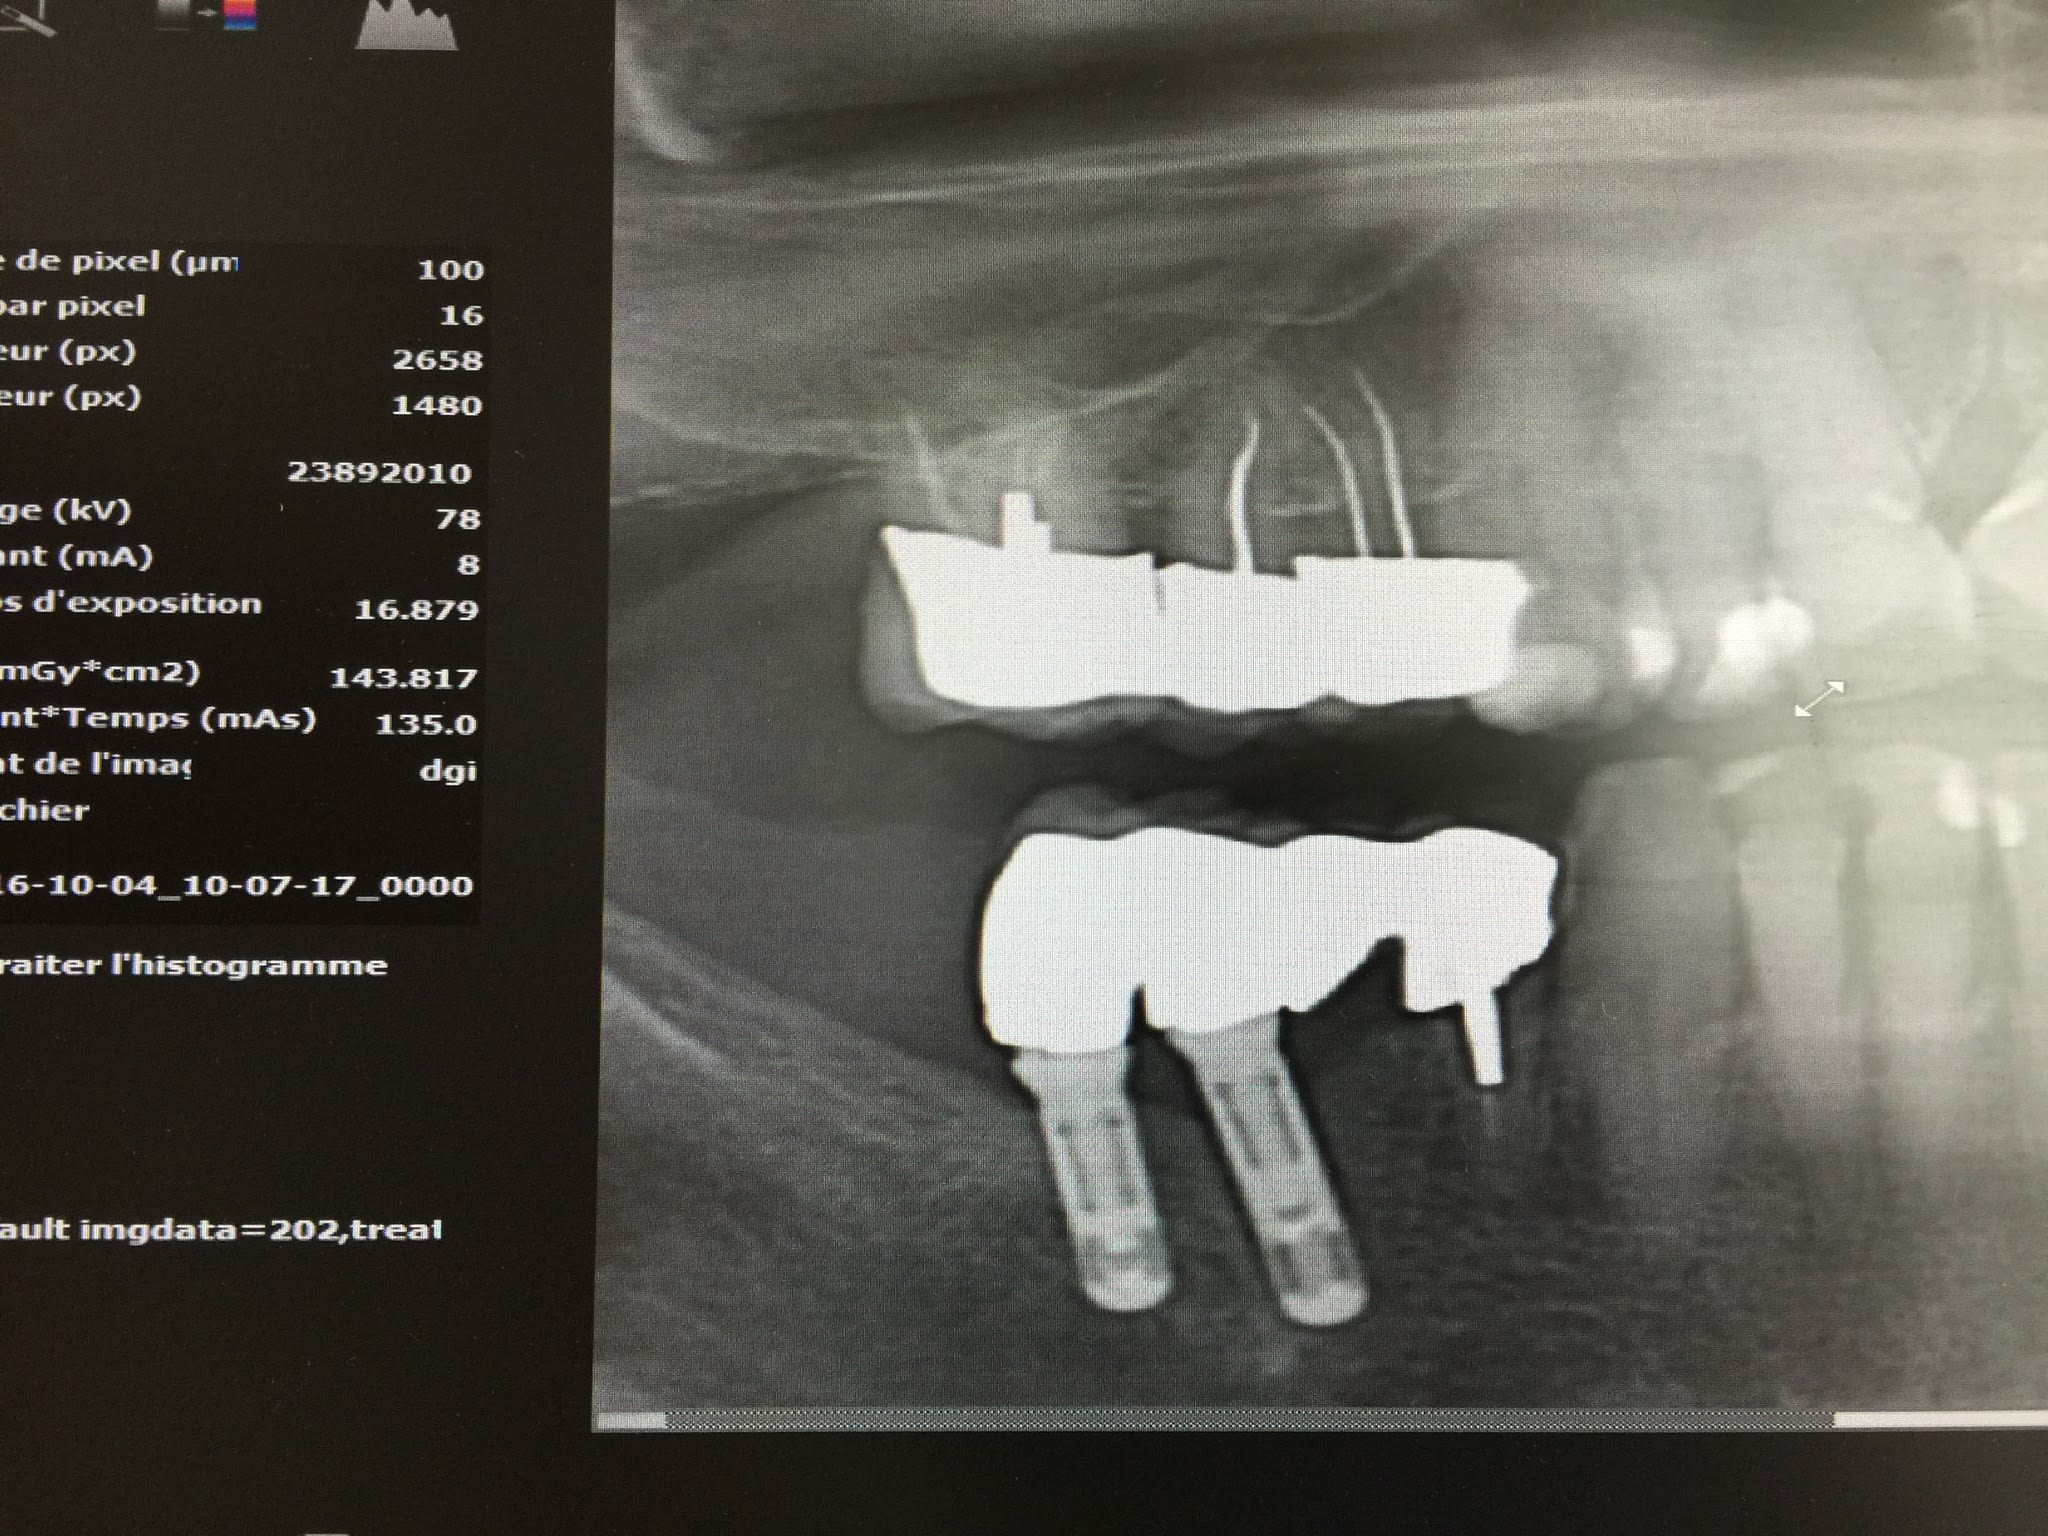

Ma patiente a un implant Straumann sur la 36.

Par contre,sur la 46 et 47, je ne connait pas la marque de ces implants(posé en 1998).

Ocexd8ufabaqccpcs1hk - Eugenol

Mey2matxilmszv8atlko - Eugenol

Ihupbjiothagj9khfkxf - Eugenol

non...

avec le double filetage interne....ce sont des... camlog...;-)

http://whatimplantisthat.com/implant/cylinder-line-5/

http://osseosource.com/dental-implants/product_info.php?manufacturers_id=19&products_id=159

J'ai oublié de vous dire qu'apparemment la tête de vis n'est pas un hexagone interne mais une sorte de vis avec seulement une tête plate avec un trait au milieu(un peu comme une vis de bricolage!!)

Le pilier est dévissé mais pas entièrement et j'ai pu voir la tête de vis.

Sinon pluton,tu es sûr que c'est des camlog?

Ce sont des diametre 4?

sûr que c'est du camlog...

pour le diamètre, c'est toi qui peut le dire en faisant une estimation avec la rétroalvéolaire....

amha c'est du 3.8 ou du 4.3...